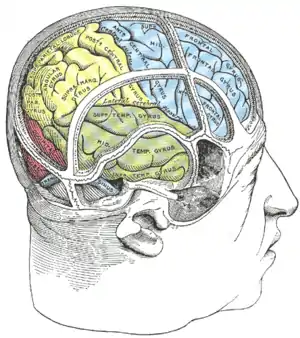

Drawing of a cast to illustrate the relations of the brain to the skull. (Angular gyrus labeled at upper left, in yellow section.) | |